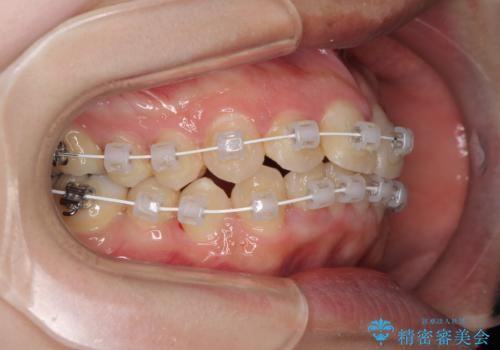

短期間で終了 デコボコをワイヤー矯正で解消

- 上下のデコボコと前歯のクロスバイトを改善したいとのことで来院された患者様です。

極力短期間で治療したいとのことで、ワイヤー装置による矯正治療を行うこととしました。

マウスピースによる矯正治療も提案しましたが、ご自身でのマウスピースの管理の面倒くささと、なるべく早く治療を終えたいとのことで、ワイヤー矯正を選択されました。